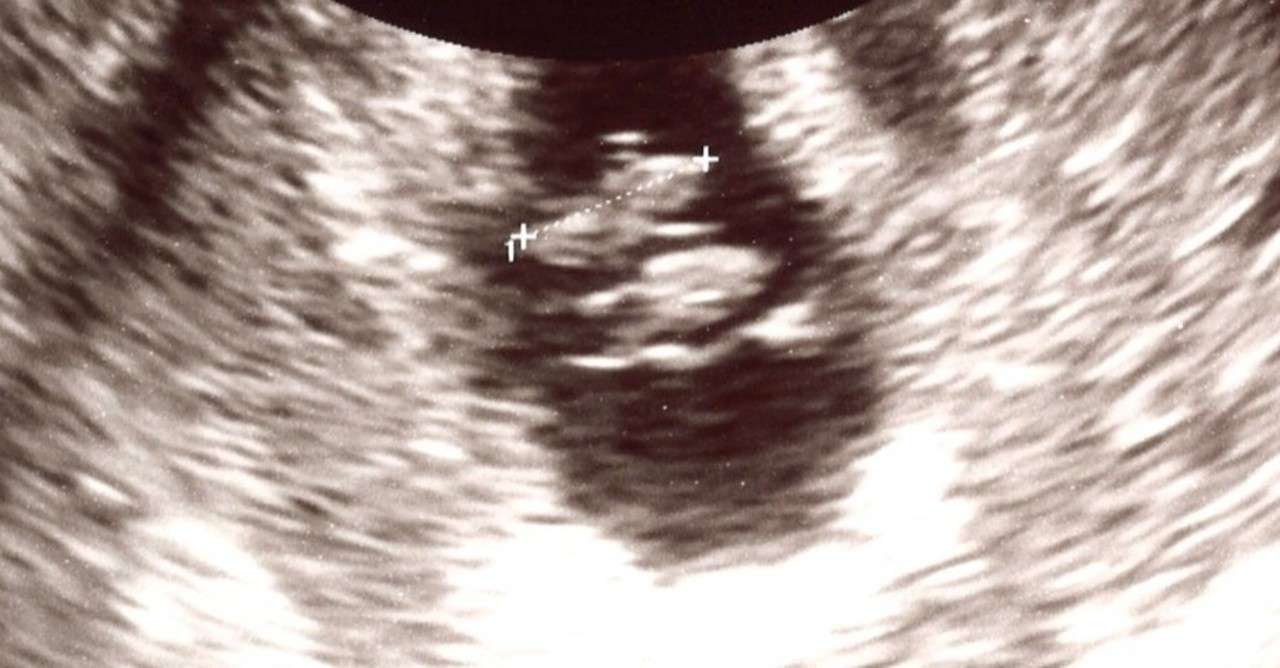

一卵性双子 エコー写真 7週. 一卵性と二卵性では、双子発覚の時期が違う? 一卵性と二卵性では、双子と判明する時期に、少々差が出るようです。 それは、胎嚢の数が違うからです。 妊娠6~7週のお腹をエコーで見ると、下記のように見えます。. こんにちは!2歳*男女の双子を育児中のまりーです^^ 「男女の双子 」ということはほぼ確実に二卵性です。 赤ちゃんが大きくなると別々で撮影されますので、双子が同時にうつっているのエコー写真は数少なく貴重なんです^^ そんなエコー写真、双子がわかった5週目から29週までを忘備録. 16年の出生時週数をグラフにしてみたよ。 青いバーが単産(1人)で赤いバーが複産(双子)です。 0〜80まで表示されている数字はパーセントです。 例えば、双子は全体の約70%が36〜39週の間に産まれていることになります。 やっぱり双子は単産に比べると早く産まれる傾向にあるのね。.

妊娠7週2日 7w2d の超音波 エコー 写真

7週 初回検診で双子妊娠が判明 心拍も二人分確認ができました Taekoのocへいこう